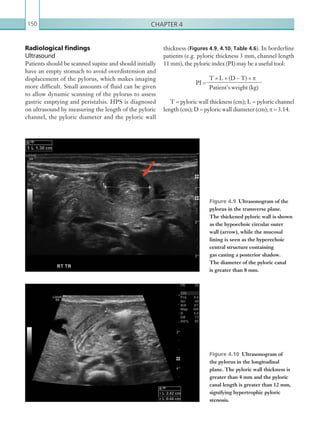

7Thoracic imaging • Carefulwindowing is required to identify dissection flaps. Intramural haematoma appears as crescenteric high attenuation material within the aortic wall on the unenhanced phase. Report checklist • Presence or absence of intramural haematoma. • Cranial and caudal extent of the dissection flap. • Patency of great vessels/coeliac axis/SMA/IMA/ renal arteries. • Presence of pericardial blood and any signs of cardiac tamponade. • Classification. Reference Macura JK, Corl FM, Fishman EK et al. (2003) Pathogenesis in acute aortic syndromes: aortic dissection, intramural hematoma, and penetrating atherosclerotic aortic ulcer. Am J Roentgenol 181:309–316. Figure 1.6  Axial image: IV contrast enhanced CT scan of the thorax in the arterial phase. A small outpouching of contrast can be seen through a defect in the distal aspect of the aortic arch, representing an atherosclerotic ulcer (arrow). THORACIC AORTIC INJURY Aorticinjuryisamajorconcerninthesettingofprimarily blunt,butalsopenetrating,thoracictrauma.Traumatic injury of the thoracic aorta is a spectrum of injury, including aortic intramural haematoma and dissection, laceration, pseudoaneurysm (in which a rupture is containedbyperiaorticsofttissues)andcompleteaortic transection and rupture (see Acute aortic syndrome for discussion on aortic intramural haematoma and dissection). Injury occurs most commonly at regions of aortic tethering, such as the aortic isthmus. Classic symptoms and signs include chest pain, dyspnoea and upper limb hypertension with associated lower limb hypotension. Ultimately, aortic transection and rupture result in profound haemodynamic instability. Mortality rates are high, estimated at 80–90% in untreated aortic injury (Parmley et al., 1958). As such, the on-call radiologist should have a high index of suspicion for aortic injury in this scenario. Accurate and swift diagnosis is vital, facilitating urgent surgical or interventional repair. Radiological investigations CT is the most sensitive and specific modality for aortic trauma. Both enhanced and unenhanced phases should be performed, the latter aiding in identification of intramural haematoma, although often the precise protocol is determined by departmental polytrauma guidelines. Depending on the clinical presentation of the patient, chest plain film imaging can be used as an initial screening test, although this modality is not reliable enough to exclude more subtle injury and can appear normal in up to 7% of significant aortic injuries (Fabian et al., 1997). (See Table 1.3.) MODALITY PROTOCOL CT Unenhanced. Scan from aortic arch to diaphragm level. Aortic angiogram: 100 ml IV contrast via 18G cannula, 4 ml/sec. Bolus track centred on the aortic arch. Scan from aortic arch to diaphragm level. Table 1.3 Thoracic aortic injury. Imaging protocol. K22247_C001.indd 7 16/05/15 3:06 AM

• 30.

Chapter 18 as haematoma.Any loss of definition of the aortic wall should also be treated with suspicion, as should focal periaortic fat stranding. Focal filling defects within the aortic lumen can indicate intraluminal clot and occult injury, although comparison with previous imaging is helpful to assess for pre-existing atheroma (Figure 1.9). Aortic dissection and intramural haematoma can also be seen in traumatic aortic injury (see Acute aortic syndrome for these findings). Any suspicion of aortic injury should be urgently communicated to the referring team. Plain films While chest plain film imaging cannot exclude aortic injury, it can yield helpful signs. Mediastinal widening of 8cm canbeanindicator of mediastinal haematoma. It should be noted that the sensitivity and specificity of mediastinal widening for aortic injury varies from 53–100% and 1–60%, respectively (Groskin, 1992). The most common cause of mediastinal haematoma in trauma is the tearing of small mediastinal veins, as opposed to aortic injury. Other signs of aortic injury include an indistinct aortic contour, left apical pleural cap, tracheal deviation and depression of the left main bronchus. Radiological findings Computed tomography As with all polytrauma cases, a ‘primary survey’ of CT imaging should be performed in an attempt to identify immediately life-threatening aortic injury. The thoracic aorta should be scrutinised using multiplanar reformatting and appropriate window settings (window 400, level 100). Focal aortic contour deformities (including focal aneurysms) and mural discontinuity are direct signs of aortic injury (Figures 1.7a, b). Familiarity with the normal appearance of the aortic isthmus is essential, since this canbemistakenforaorticinjury.Activeextravasationof IVcontrast,commonlyintothemediastinumorpleural spaces, is indicative of active bleeding. There are more subtle signs of aortic injury. The presence of mediastinal haematoma should always make the on-call radiologist suspicious, although other causes include venous injury (including the azygous vein) and vertebral body fractures. Mediastinal haematoma presents on CT as increased attenuation material within the mediastinum (30 Hu). Periaortic haematoma is extremely worrisome for an occult aortic injury (Figures 1.8a, b). Both residual thymic tissue and pericardial recesses can be misinterpreted Figures 1.7a, b  Axial and coronal images: IV contrast enhanced CT scans of the thorax in the arterial phase. Both cases demonstrate contour abnormality of the thoracic aorta, in keeping with aortic injury (arrows). (a) (b) K22247_C001.indd 8 16/05/15 3:06 AM

• 31.

9Thoracic imaging References Fabian TC,Richardson JD, Croce MA et al. (1997) Prospective study of blunt aortic injury: multicenter trial of the American Association for the Surgery of Trauma. J Trauma Acute Care Surg 42:374–380; discussion 380–383. Groskin SA (1992) Selected topics in chest trauma. Radiology 183:605–617. Parmley LF, Mattingly TW, Manion WC et al. (1958) Nonpenetrating traumatic injury of the aorta. Circulation 17:1086–1101. Figure 1.9  Axial image: IV contrast enhanced CT scan of the thorax in the arterial phase. There is a filling defect within the aortic lumen, in keeping with a clot (arrow). Periaortic haematoma is also present. Figures 1.8a, 8b  Axial images: IV contrast enhanced CT scans of the thorax in the arterial phase. There is increased density material in the para-aortic regions consistent with haematoma (arrows). This can be seen tracking inferiorly in the posterior mediastinum along the descending thoracic aorta. An aortic dissection flap can be seen within the aortic lumen (1.8a). Key points • Aortic injury is a life-threatening complication of both blunt and penetrating trauma. • CT is the modality of choice to investigate aortic injury but radiological signs may also be seen on plain film radiographs. Report checklist • Document the relevant negatives of thoracic aortic injury, including aortic contour abnormality, mediastinal haematoma and active extravasation. • Recommend urgent surgical and interventional radiology opinion. (a) (b) K22247_C001.indd 9 16/05/15 3:06 AM

• 32.